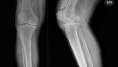

Dizden Çıkan Eklem Fareleri Şaşırttı!